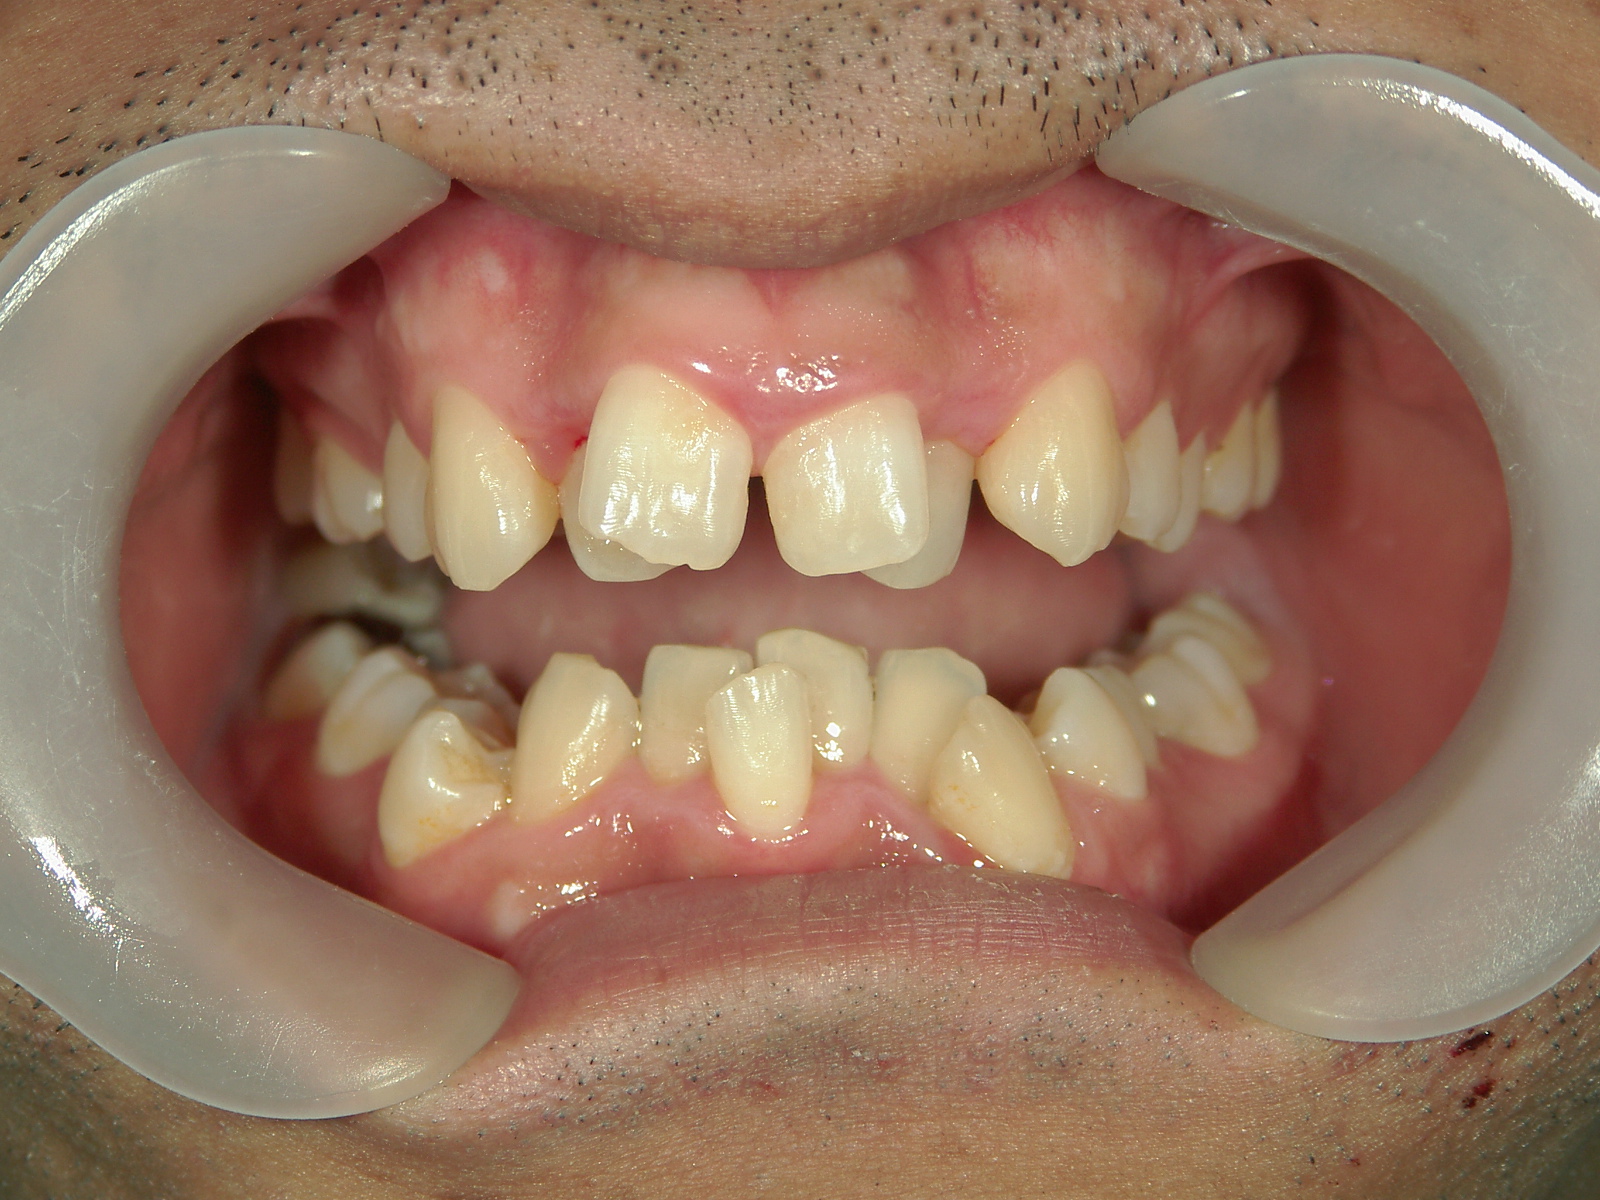

全顎ワイヤー矯正 症例(79)

主訴: 前歯が噛み合わない。歯並びが気になる。

上下左右 第一小臼歯(4本)、上下右 親不知(2本)抜歯。

ミニインプラント、アップライトスプリングを併用。

カテゴリー : ガタガタ(叢生) , 噛み合わせが深い(過蓋咬合)